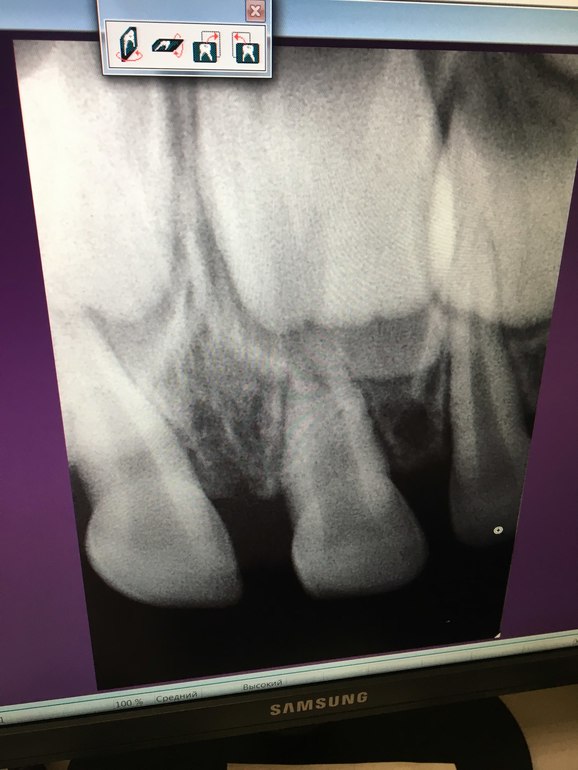

очень нужна еще одна консультация стоматолога, помогите, пожалуйста, ребенок несколько месяцев назад упал и ударился зубом, он потемнел, сходили сделали снимок, сказали, что связка повреждена и наблюдать, вот вчера еще раз сходили сделали снимок и сказали, что есть небольшая подвижность и что корень этого зуба уменьшается и нужно удалять((((((( ребенку 2г11 мес. Подскажите, пожалуйста, действительно нужно удалять?

прилагаю фото двух рентгенов

Не вижу показаний к удалению зуба.

Да, корень стал короче. Но это не повод лишаться зуба

Я бы рекомендовала удалить нерв из зуба и запломбировать канал. Возможно, когда-нибудь все же потребуется удалить. Что мало вероятно. В моей практике такие зубы менялись по возрасту самостоятельно.

И нужно будет бережно относиться к нему. Т.к. возможность полного вывиха зуба в результате травмы, например, с укороченным корнем выше, чем в обычных ситуациях